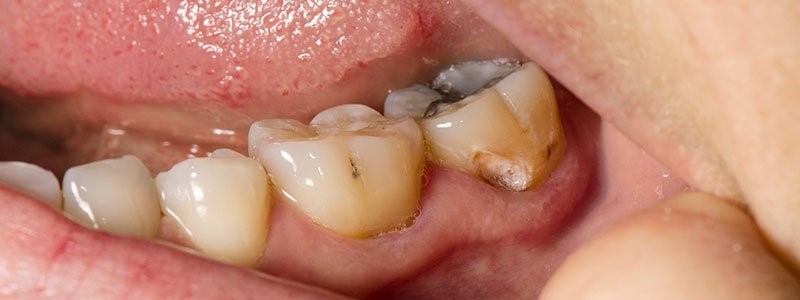

- آبسه پری اپیکال: در این حالت باکتری ها از طریق پوسیدگی وارد دندان های شما می شوند و پالپ و قسمت های نرم داخلی دندان را تحت تاثیر خود قرار می دهند. این قسمت از دندان حاوی اعصاب و رگهای خونی است و به راحتی آسیب می بیند.

عدم رعایت بهداشت دهان و دندان به مرور زمان منجر به رشد باکتری ها در اطراف دندان ها و لثه های شما میشود که طبیعتاً نتیجه فعالیت آنها عفونت دندان و در نهایت آبسه دندان است. اما به طور کلی نحوه این اتفاق به نوع آبسه هم بستگی دارد: